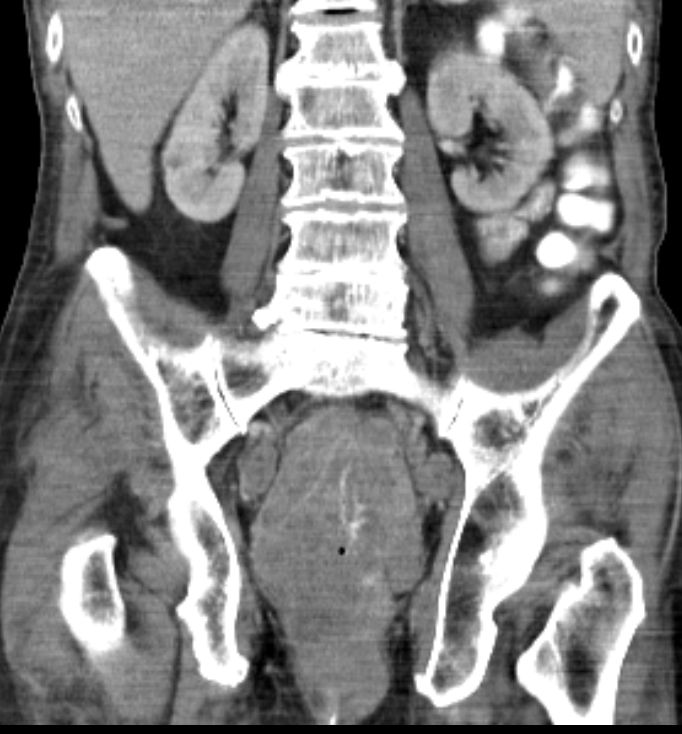

| Colitis | 77-jähriger Mann, der vor 2 Jahren mit Colitis ulcerosa eingeliefert wurde. Das CT zeigte eine diffuse Wandverdickung des gesamten Kolonrahmens mit Infiltration des umgebenden Fettgewebes. Umschriebene Perforation des Rektums nach ventral zur Prostata ohne Nachweis einer rektrourethralen Fistel. Endoskopie mit Biopsien: keine Malignität. | |

| Tumor | Jetzt Wiederaufnahme wegen eines akuten Schubs der Colitis ulceosa. Ausgedehnter Rektum - Tumor, welchen das kleine Becken ausfüllt. Zirkuläres, exophytisch und ulzerierend und infiltrierend wachsendes Karzinom im Rektum und Analkanal. Lebermetastasen. | |